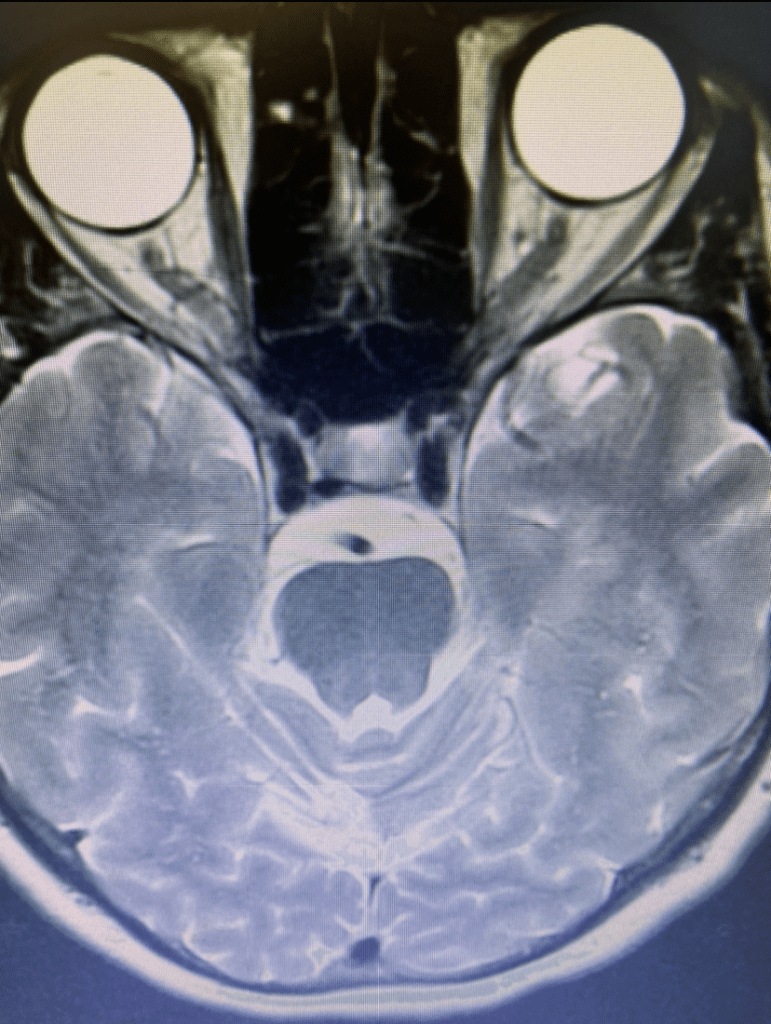

She returned for a follow up visit 19 years after the Gamma Knife treatment just to check up on things. She felt well and was neurologically intact. MRI and CTA of the brain were performed, which demonstrated complete obliteration of the AVM.

Figure 2C. Axial CTA image.